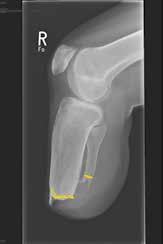

Die Länge des Knochens ist für die Biomechanik des Stumpfes wesentlich verantwortlich. Sie richtet sich nach der Beschaffenheit der Weichteile und der Durchblutung des Unterschenkels. Vom Knochen wird prinzipiell nicht das Periost entfernt. Die Tibia wird ventral angeschrägt, so dass besonders bei kürzeren Stümpfen noch eine breite Endkontaktfläche (Spongiosa) verbleibt (Abb. 13). Im distalen Bereich (langer US-Stumpf), also im Röhrenknochenanteil, sollte man die Knochenkanten gut brechen, damit kein zusätzlicher Druck von innen gegen die dort geringen Weichteile (Haut, Sehnen) herrscht.

Im Folgenden werden anhand von Fotos aus dem Archiv des Verfassers einige einschlägige Fälle vorgestellt, um häufig vorkommende Fehler aufzuzeigen (Abb. 1–10).